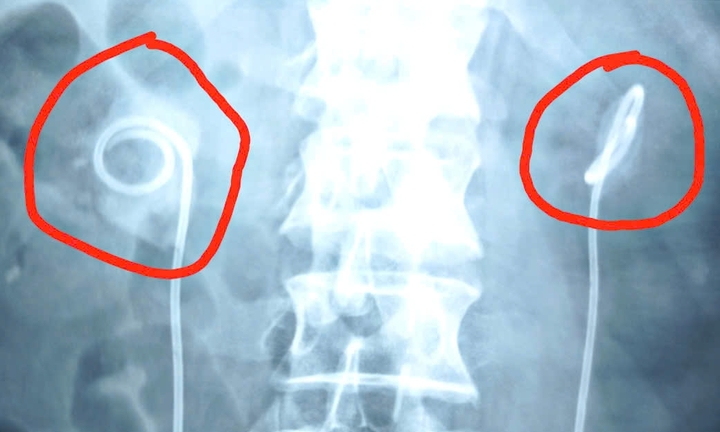

Người đàn ông suýt ngừng tim do biến chứng nặng khi để ống thông JJ trong cơ thể suốt hai năm không rút theo chỉ định.